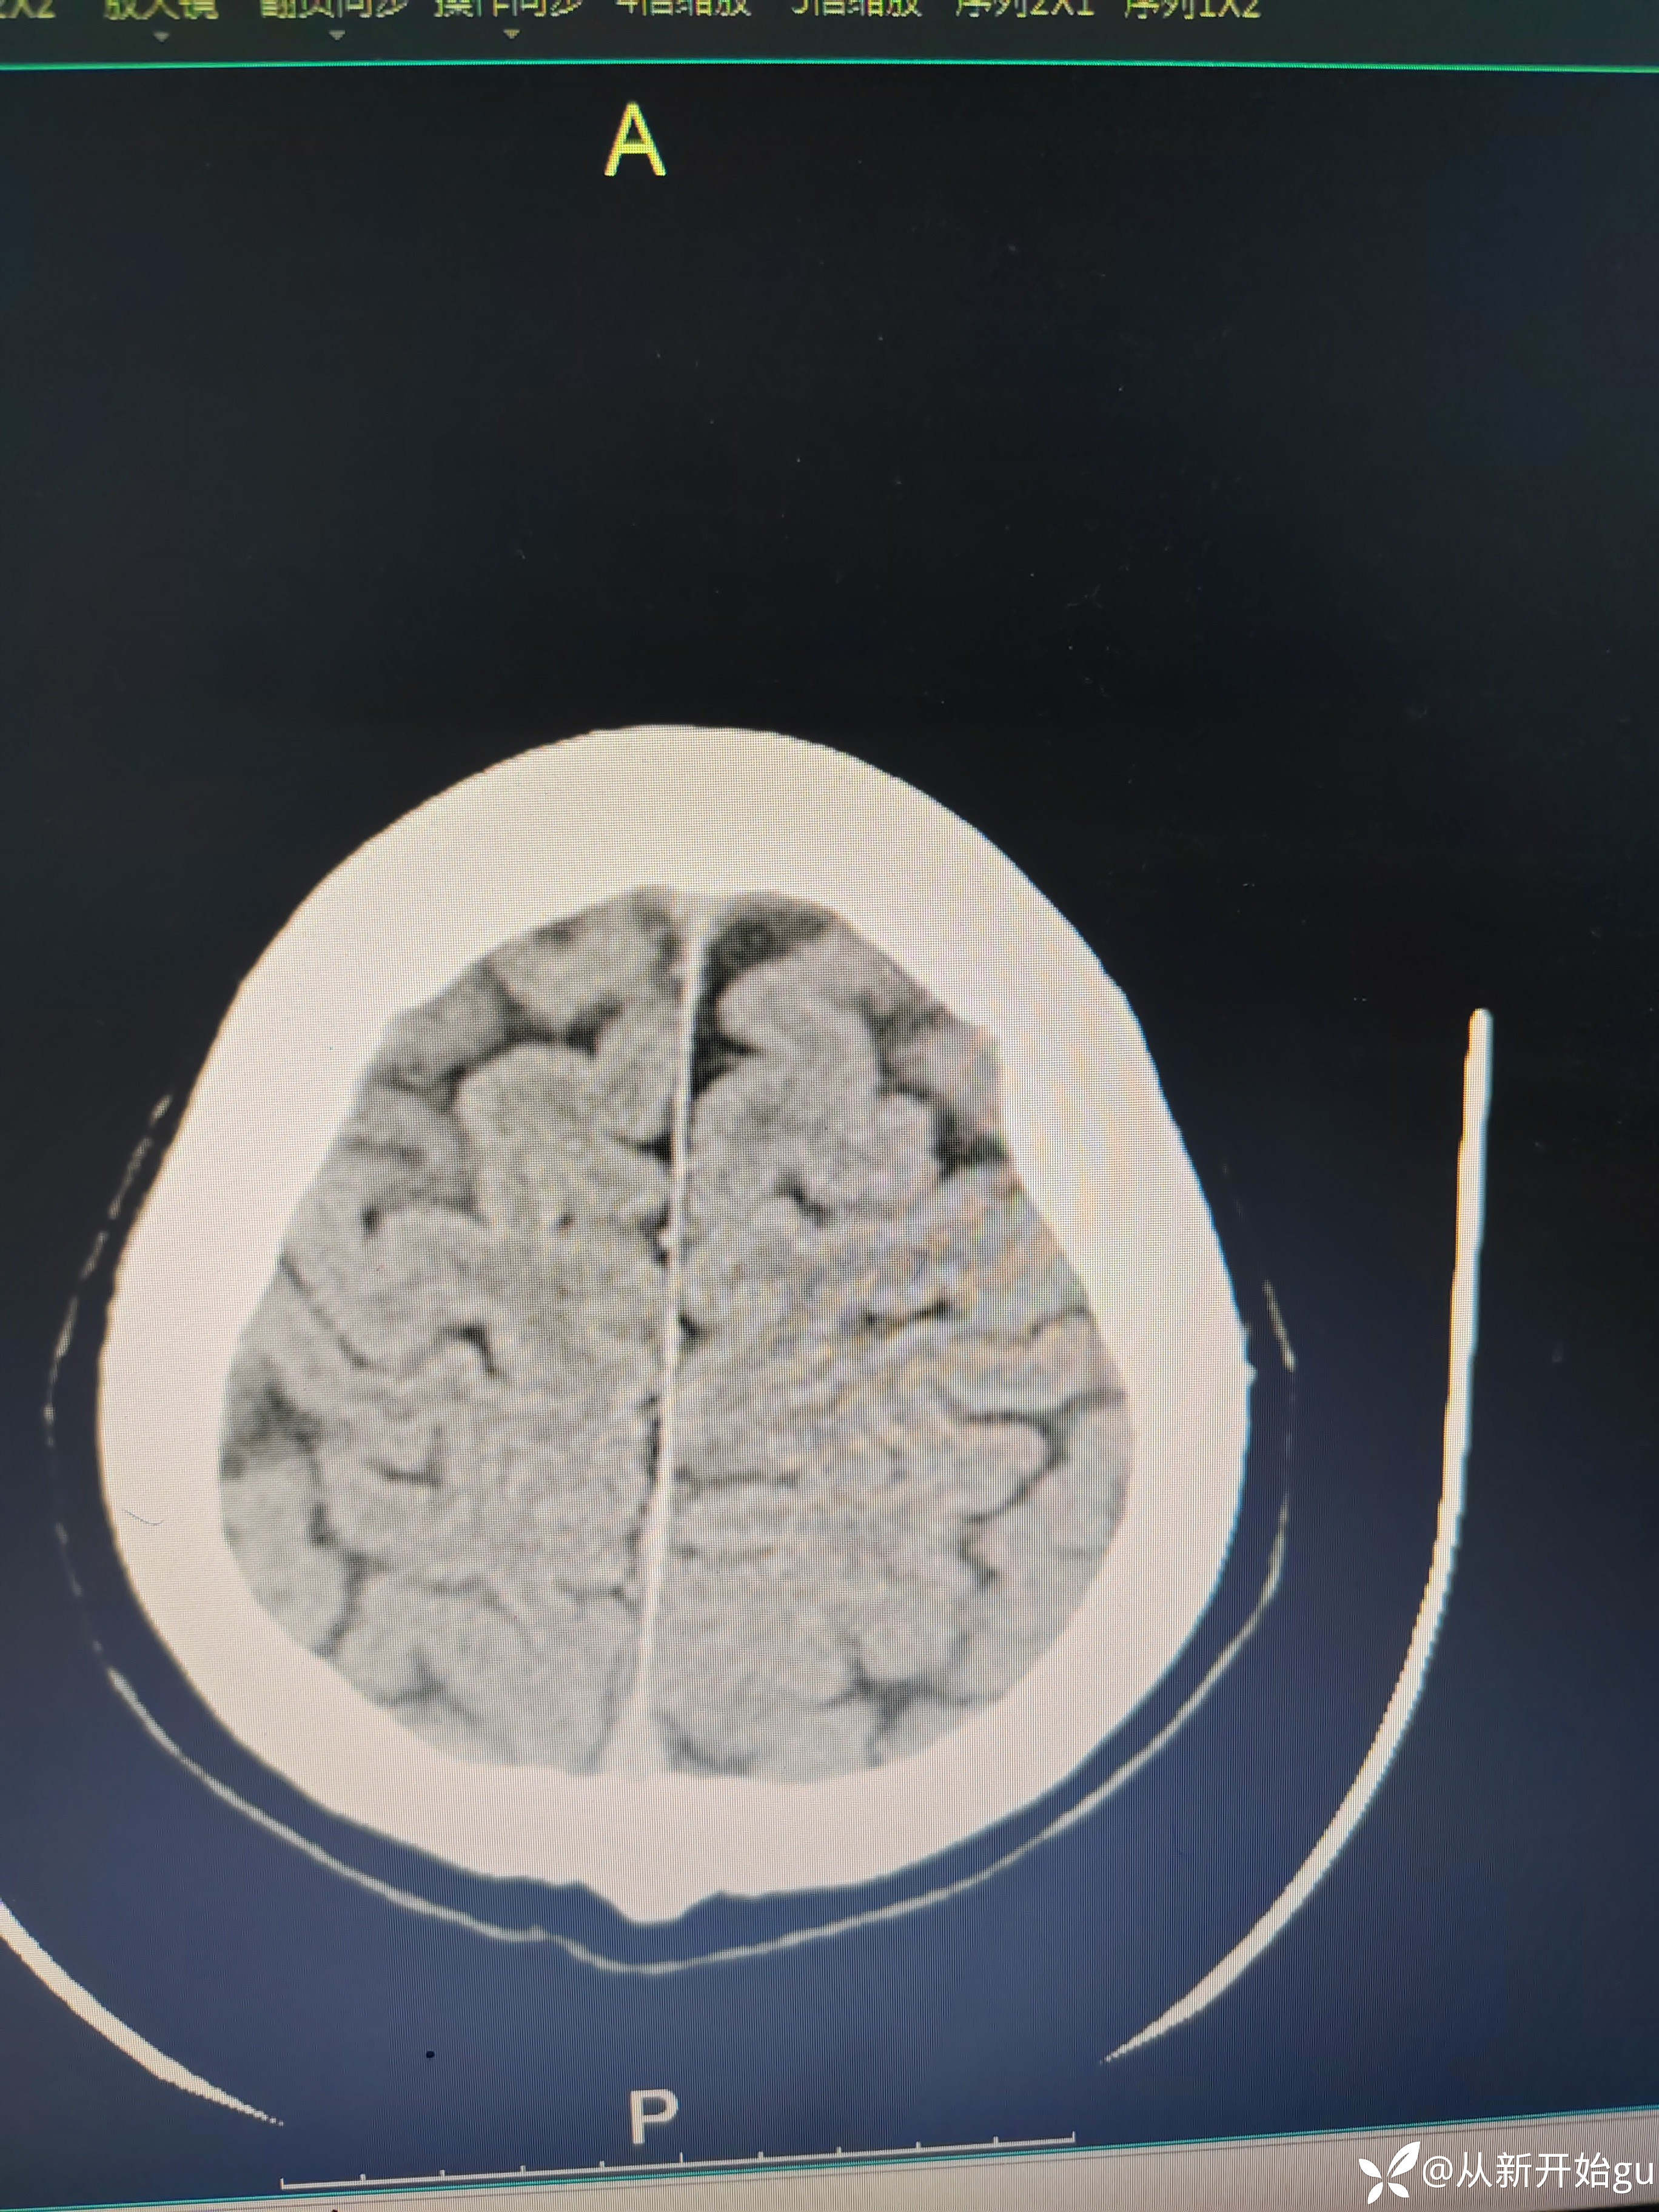

患者左下肢屈膝位—伸直过程中,左下肢费力感,左下肢僵硬感。常规我是会做个DWi明确一下,晚上都11点了(心疼放射科兄弟,就没做),直接和家属谈了一句溶栓,简要的说明,可溶可不溶,考虑病灶比较小(致残不致残都承担着同样的风险,个人不太想给溶)。家属比较积极,最后给予溶栓治疗。溶栓后无明显改善,第二天晨起诉明显减轻,但较正常下肢还是有区别。完善核磁检查(发病10小时做的)无新发梗死灶。血管如图所示: